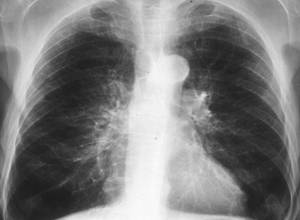

- Рентгенография позволяет исключить другие заболевания легких, обнаружить признаки других патологий, а также выявить деформацию корней легких и наличие эмфиземы;